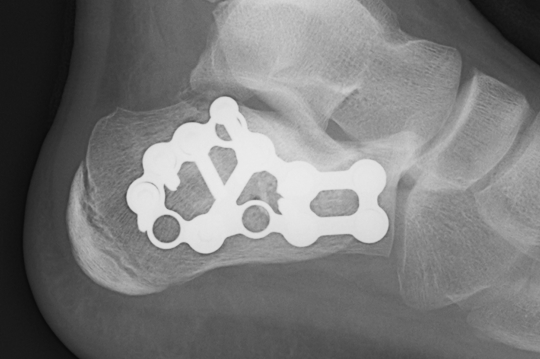

ORIF lateral plate using extensile lateral approach

Depuy Synthes calcaneal locking plates PDF

Technique

AO surgery reference extensile lateral approach

AO surgery calcaneal ORIF lateral plate

Extensile lateral approach

- vertical limb: between tendoachilles and fibula

- horizontal limb: in line with 5th metatarsal towards CC joint

- full thickness flaps - care ++++ with apex of incision

- divide peroneal retinaculum

- peroneal tendons elevated

K wires to retract skin flap

- 2 in talus / 1 in fibula

Expose subtalar joint

Reduction of varus

- Steinmann pin into tuberosity

- can elevate and pull out of varus

Reduction of subtalar joint

- open lateral wall fragment to access to subtalar joint

- lamina spreader

- reduce and ORIF with screws

- reduce and ORIF sustentaculum fragment

Anatomical contoured locking plate